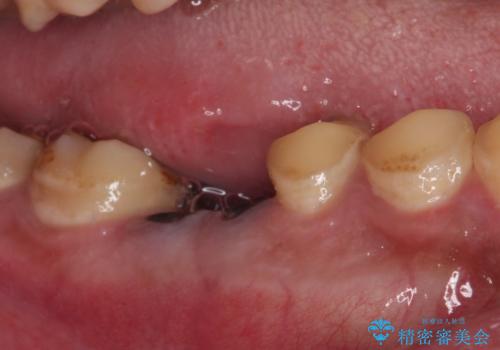

- 奥歯が痛く、放置した虫歯があるとのことで来院された患者様です。

全体的に汚れが多く、歯の表面の脱灰が全体的に認められましたが、まずは奥歯の虫歯治療から行うこととしました。

根っこだけとなっている歯は抜歯をし、奥の大きな虫歯となっている歯は、神経を取り除く可能性を考慮しながら処置を進めて行くこととしました。